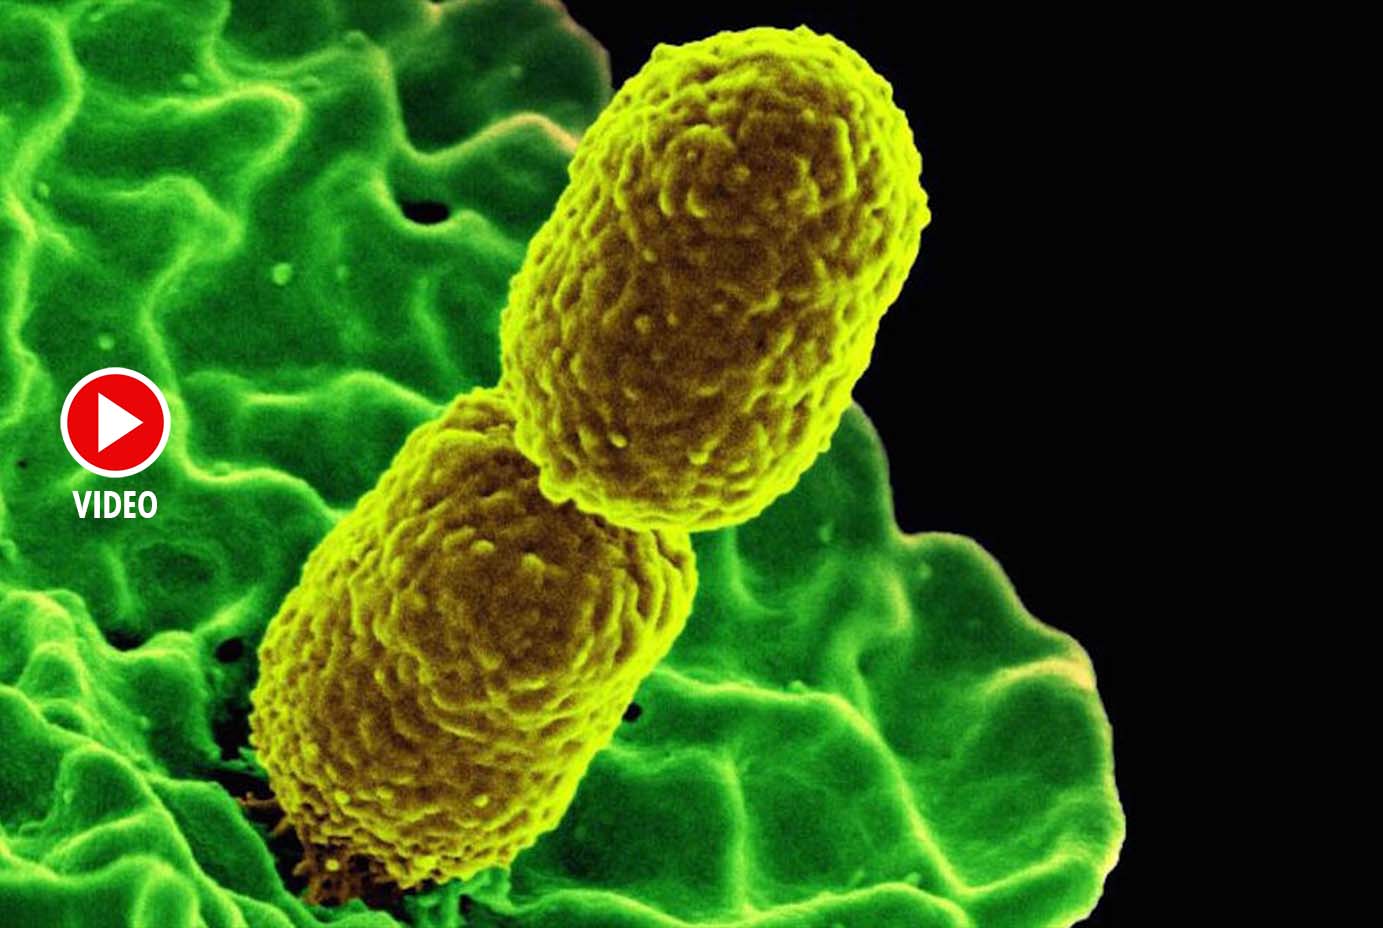

Фотографии бактерий, вызывающих бактериальные пневмонии у животных